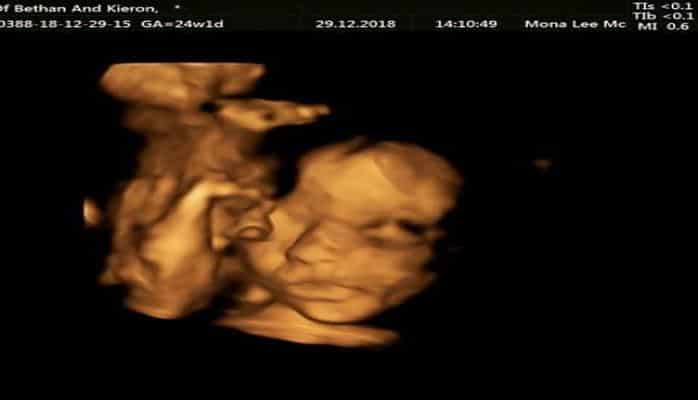

Milli.Az xarici mətbuata istinadla xəbər verir ki, Belçikada doğulmamış körpə ana bətnindən çıxarılaraq əməliyyat olunduqdan sonra yenidən yerinə qoyulub.

Əməliyyat Bethan Simpson adlı qadının üzərində həyata keçirilib.

Cərrahlar əməliyyatla qadının körpə qızını bətnindən çıxarıb, onurğa yırtığını tikdikdən sonra yenidən anasının bətninə yerləşdiriblər.

Belçikadakı "Great Ormond Street Hospital"da keçirilən əməliyyatı ingilis həkimlər belçikalı həmkarları ilə birgə həyata keçiriblər.